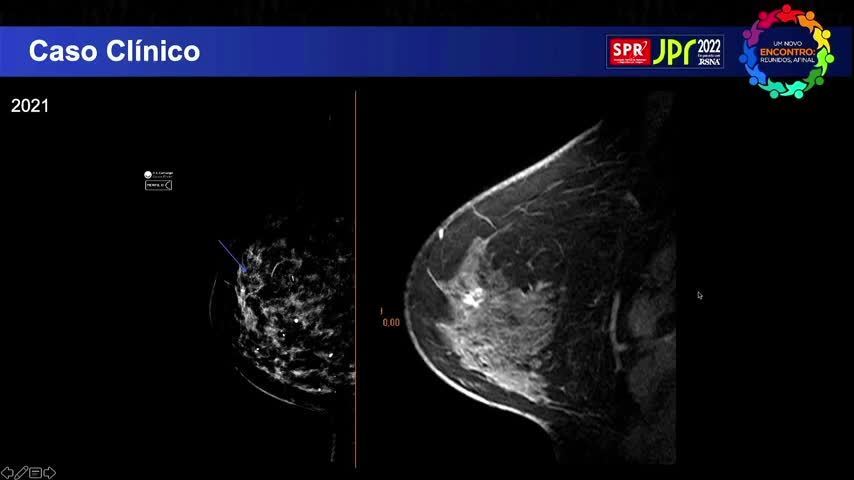

Linfoma Anaplástico de Grandes Célula...

Linfoma Anaplástico de Grandes Células Associado ao Implante - Fleury